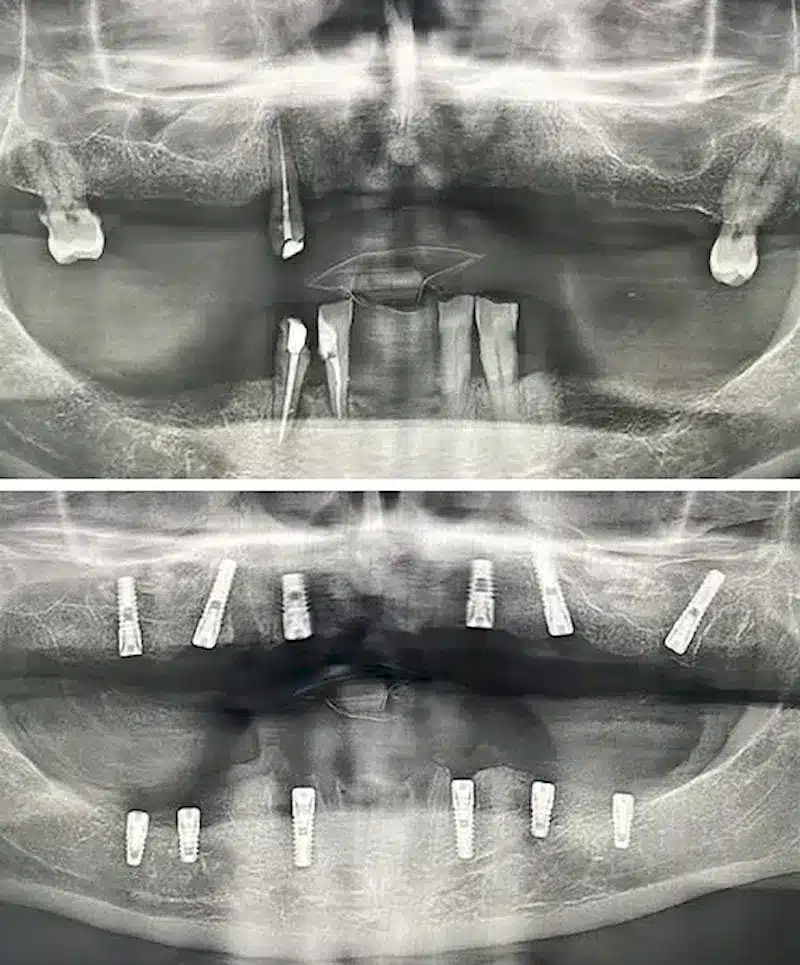

Dr. Seden Aksu is a specialist in modern implantology and surgical dentistry with extensive experience in the management of complex clinical cases. In her practice, she applies comprehensive surgical planning, minimally invasive techniques, and advanced regenerative technologies aimed at restoring both the function of the dentoalveolar system and the aesthetics of the smile. Dr. Aksu has significant experience in performing implant procedures, bone augmentation, and periodontal surgery, including the treatment of patients with severe bone loss. The primary goal of her work is to achieve stable, long-term outcomes in implant rehabilitation and the restoration of oral tissue health.